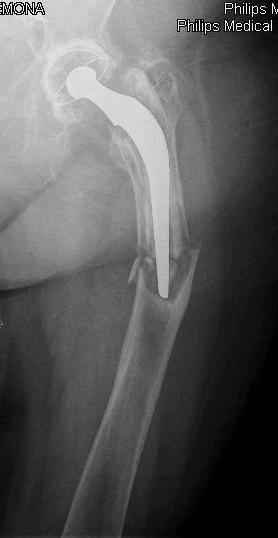

Hello! This is just illustration in one of the choice of treatment

Michael

Reminded me of a case I did a couple years ago - 30 year old woman with juvenile rheumatoid arthritis and a nonunion below her stem. Fixed with retrograde nail which docked with the stem and a lateral locking plate. Image attached. One of the companies should come up with a stem design and nail system that anticipates this need.